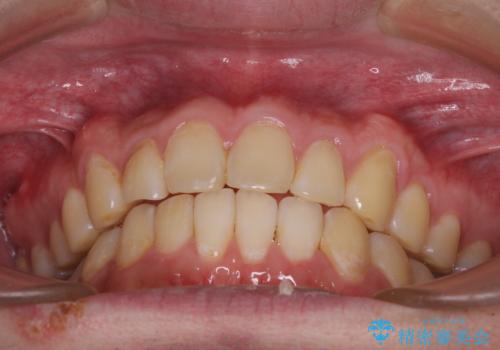

しかし、費用面や期間で悩んでいらっしゃったため、左側臼歯の問題は解決せずに前歯のデコボコのみを改善するシミュレーションを作成し、治療を行うこととしました。

写真より左側臼歯の咬合がタイトではないことが分かりますが、こちらは保定期間に徐々に咬合させていくこととしました。